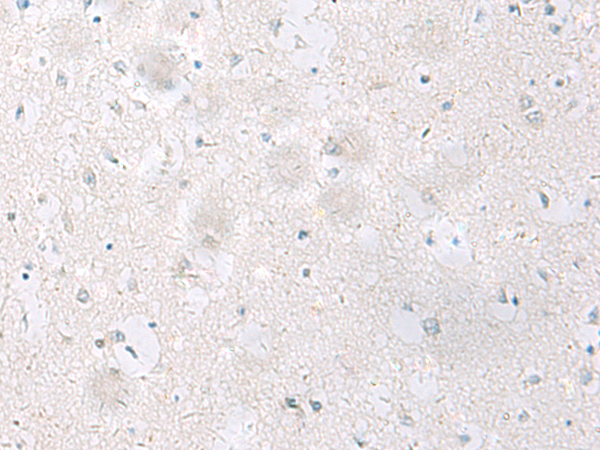

IHC positive control: |

Human brain |

IHC Recommend dilution: |

25-50 |